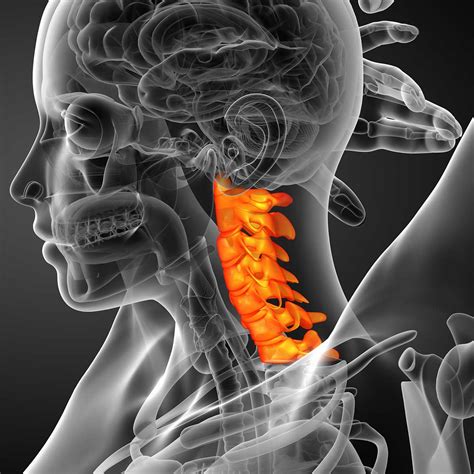

The human neck is marvelously designed with a natural, inward-curving arc known as the cervical lordosis. This gentle "C" shape is essential for supporting the weight of your head, acting as a shock absorber, and facilitating a full range of motion. However, modern lifestyle factors—ranging from prolonged screen time to poor posture—have led to an increasing prevalence of a straight cervical spine. Often referred to as "military neck" or cervical kyphosis in severe cases, the loss of this natural curvature can lead to a cascade of musculoskeletal issues. Understanding the causes, symptoms, and corrective measures for this condition is vital for anyone looking to maintain long-term neck health and spinal integrity.

What is a Straight Cervical Spine?

In a healthy neck, the cervical vertebrae align in a lordotic curve that distributes the load of your head evenly across the spine. When you have a straight cervical spine, this curvature flattens out, causing the neck to appear straight when viewed from the side on an X-ray or MRI. When this curve is lost, the weight of your head is no longer balanced, placing excessive stress on the muscles, ligaments, and intervertebral discs. This biomechanical imbalance is the root cause of many chronic neck pain complaints.